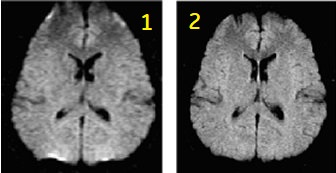

FLAIR EPI

FLAIR EPI is designed to minimize the signal from CSF on a T2-weighted EPI sequence.

| 1 | Single-shot |

| 2 | Multi-shot |